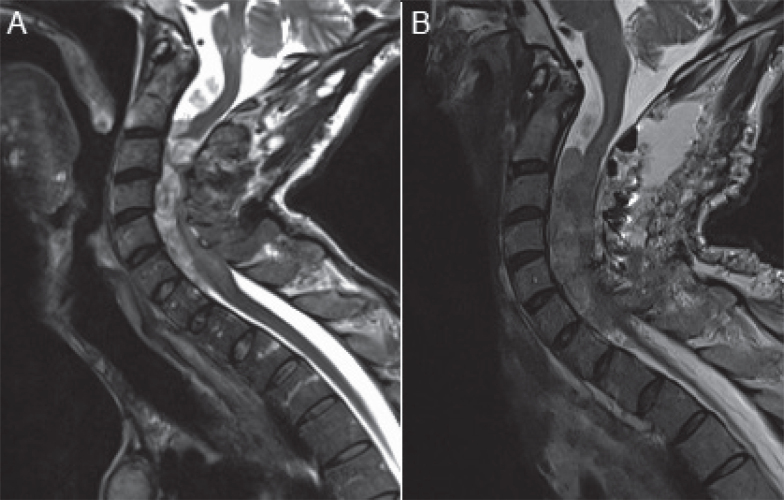

本病例是一名 35 岁男性患者,患有脊柱占位性神经纤维瘤病-1(spinal predominant neurofibromatosis-1),出现了不完全脊髓损伤(C3 Asia C),尽管对多发性颈椎神经纤维瘤进行了紧急减压手术,但病情仍不见好转。本报告概述了鞘内注射巴氯芬的新适应症。患者下肢无力并伴有严重痉挛,所有活动至少需要两人协助。康复治疗的目的是改善患者的整体肌张力,同时注重患者的独立性、活动能力和生活质量。在成功试用了鞘内巴氯芬后,他接受了鞘内巴氯芬泵植入手术。在他接受渐进式伸展和功能康复治疗的同时,剂量也在逐渐增加。6 周后,他的 MAS 已提高到 1-2/4,并已能独立转移、独立进行大多数日常生活活动,而且只需极少的支持就能出院回家。

This case presents a 35-year-old male with spinal predominant neurofibromatosis-1 who developed an incomplete spinal cord injury (C3 Asia C) which did not improve despite urgent decompressive surgery for multiple cervical neurofibromas. This report outlines a novel indication for intrathecal baclofen. The patient suffered from lower limb weakness with severe spasticity and required assistance of at least two for all activities. The aim of rehabilitation was to improve overall tone while focusing on independence, mobility and quality of life. After a successful trial of intrathecal baclofen, he underwent implantation of an intrathecal baclofen pump. The dose was gradually increased while he received a progressive programme of stretching and functional rehabilitation therapy. After 6 weeks, his MAS had improved to 1-2/4 and he had progressed to independent transfers, independence for most activities of daily living and was able to discharge to his family home with minimal support.